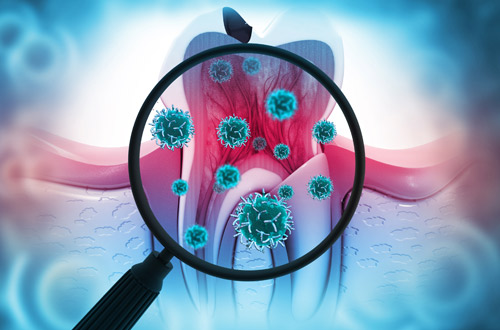

歯の汚れや黄ばみの原因

歯が汚れる原因の多くはコーヒー・紅茶・茶渋などの飲食物に含まれる色素成分のタンニンやタバコのヤニに含まれているニコチン・タールなどのステイン(歯の着色汚れ)です。

ステインは食べ物に含まれているポリフェノールが歯の表面を覆っているたんぱく質と結合し生成されます。

また、加齢に伴い歯の表面のエナメル質が薄くなり内部の象牙質の色味が強くなったり、テトラサイクリン系の抗生物質を服用し歯の奥に色が沈着し黄ばんでしまったように見えたりすることなどの要因が挙げられます。